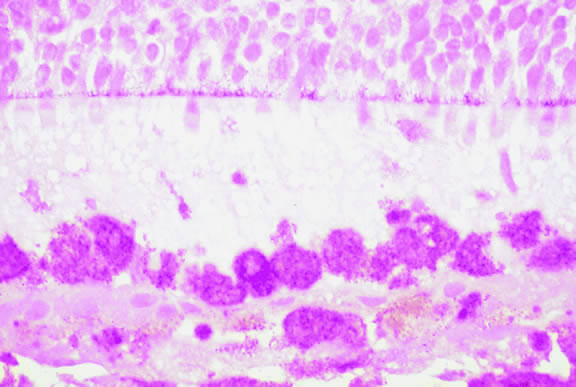

Although non-Hodgkin's lymphoma often affects the orbit and conjunctiva, intraocular involvement by lymphoma is relatively rare and occurs in two basic ways. First, patients who have widely disseminated systemic lymphoma may develop secondary ocular involvement whose typical manifestation is uveal infiltration. Second, in the variant of central nervous system (CNS) lymphoma that has been called primary lymphoma of the CNS and retina, the vitreous characteristically is involved and the uvea is spared. The latter entity also has been called vitreous large cell lymphoma or ocular “reticulum cell sarcoma.”205–208 In addition to the vitreous, the lymphoma cells also infiltrate the retina, and typically collect between Bruch's membrane and the retinal pigment epithelium, forming solid yellowish RPE detachments, which are highly suggestive of the diagnosis. This rare variant of primary CNS lymphoma should be suspected in older patients who have chronic vitritis that is unresponsive to therapy. Cytologic examination of diagnostic vitrectomy specimens reveals a highly cellular and extensively necrotic infiltrate that contains atypical lymphocytes with prominent nucleoli and protrusions of the nuclear membrane (Fig. 53). The significance of elevated vitreous interleukin 10 levels as a diagnostic marker for lymphoma is controversial.209,210

Fig. 53. Primary central nervous system lymphoma, vitreous. Diagnostic vitrectomy specimen contains large atypical lymphocytes, necrotic lymphoid cells, and nuclear debris. Lymphoma cells in inset have nuclear membrane protrusions and prominent nucleoli. Main figure, Millipore filter. (Hematoxylin-eosin, × 250.)